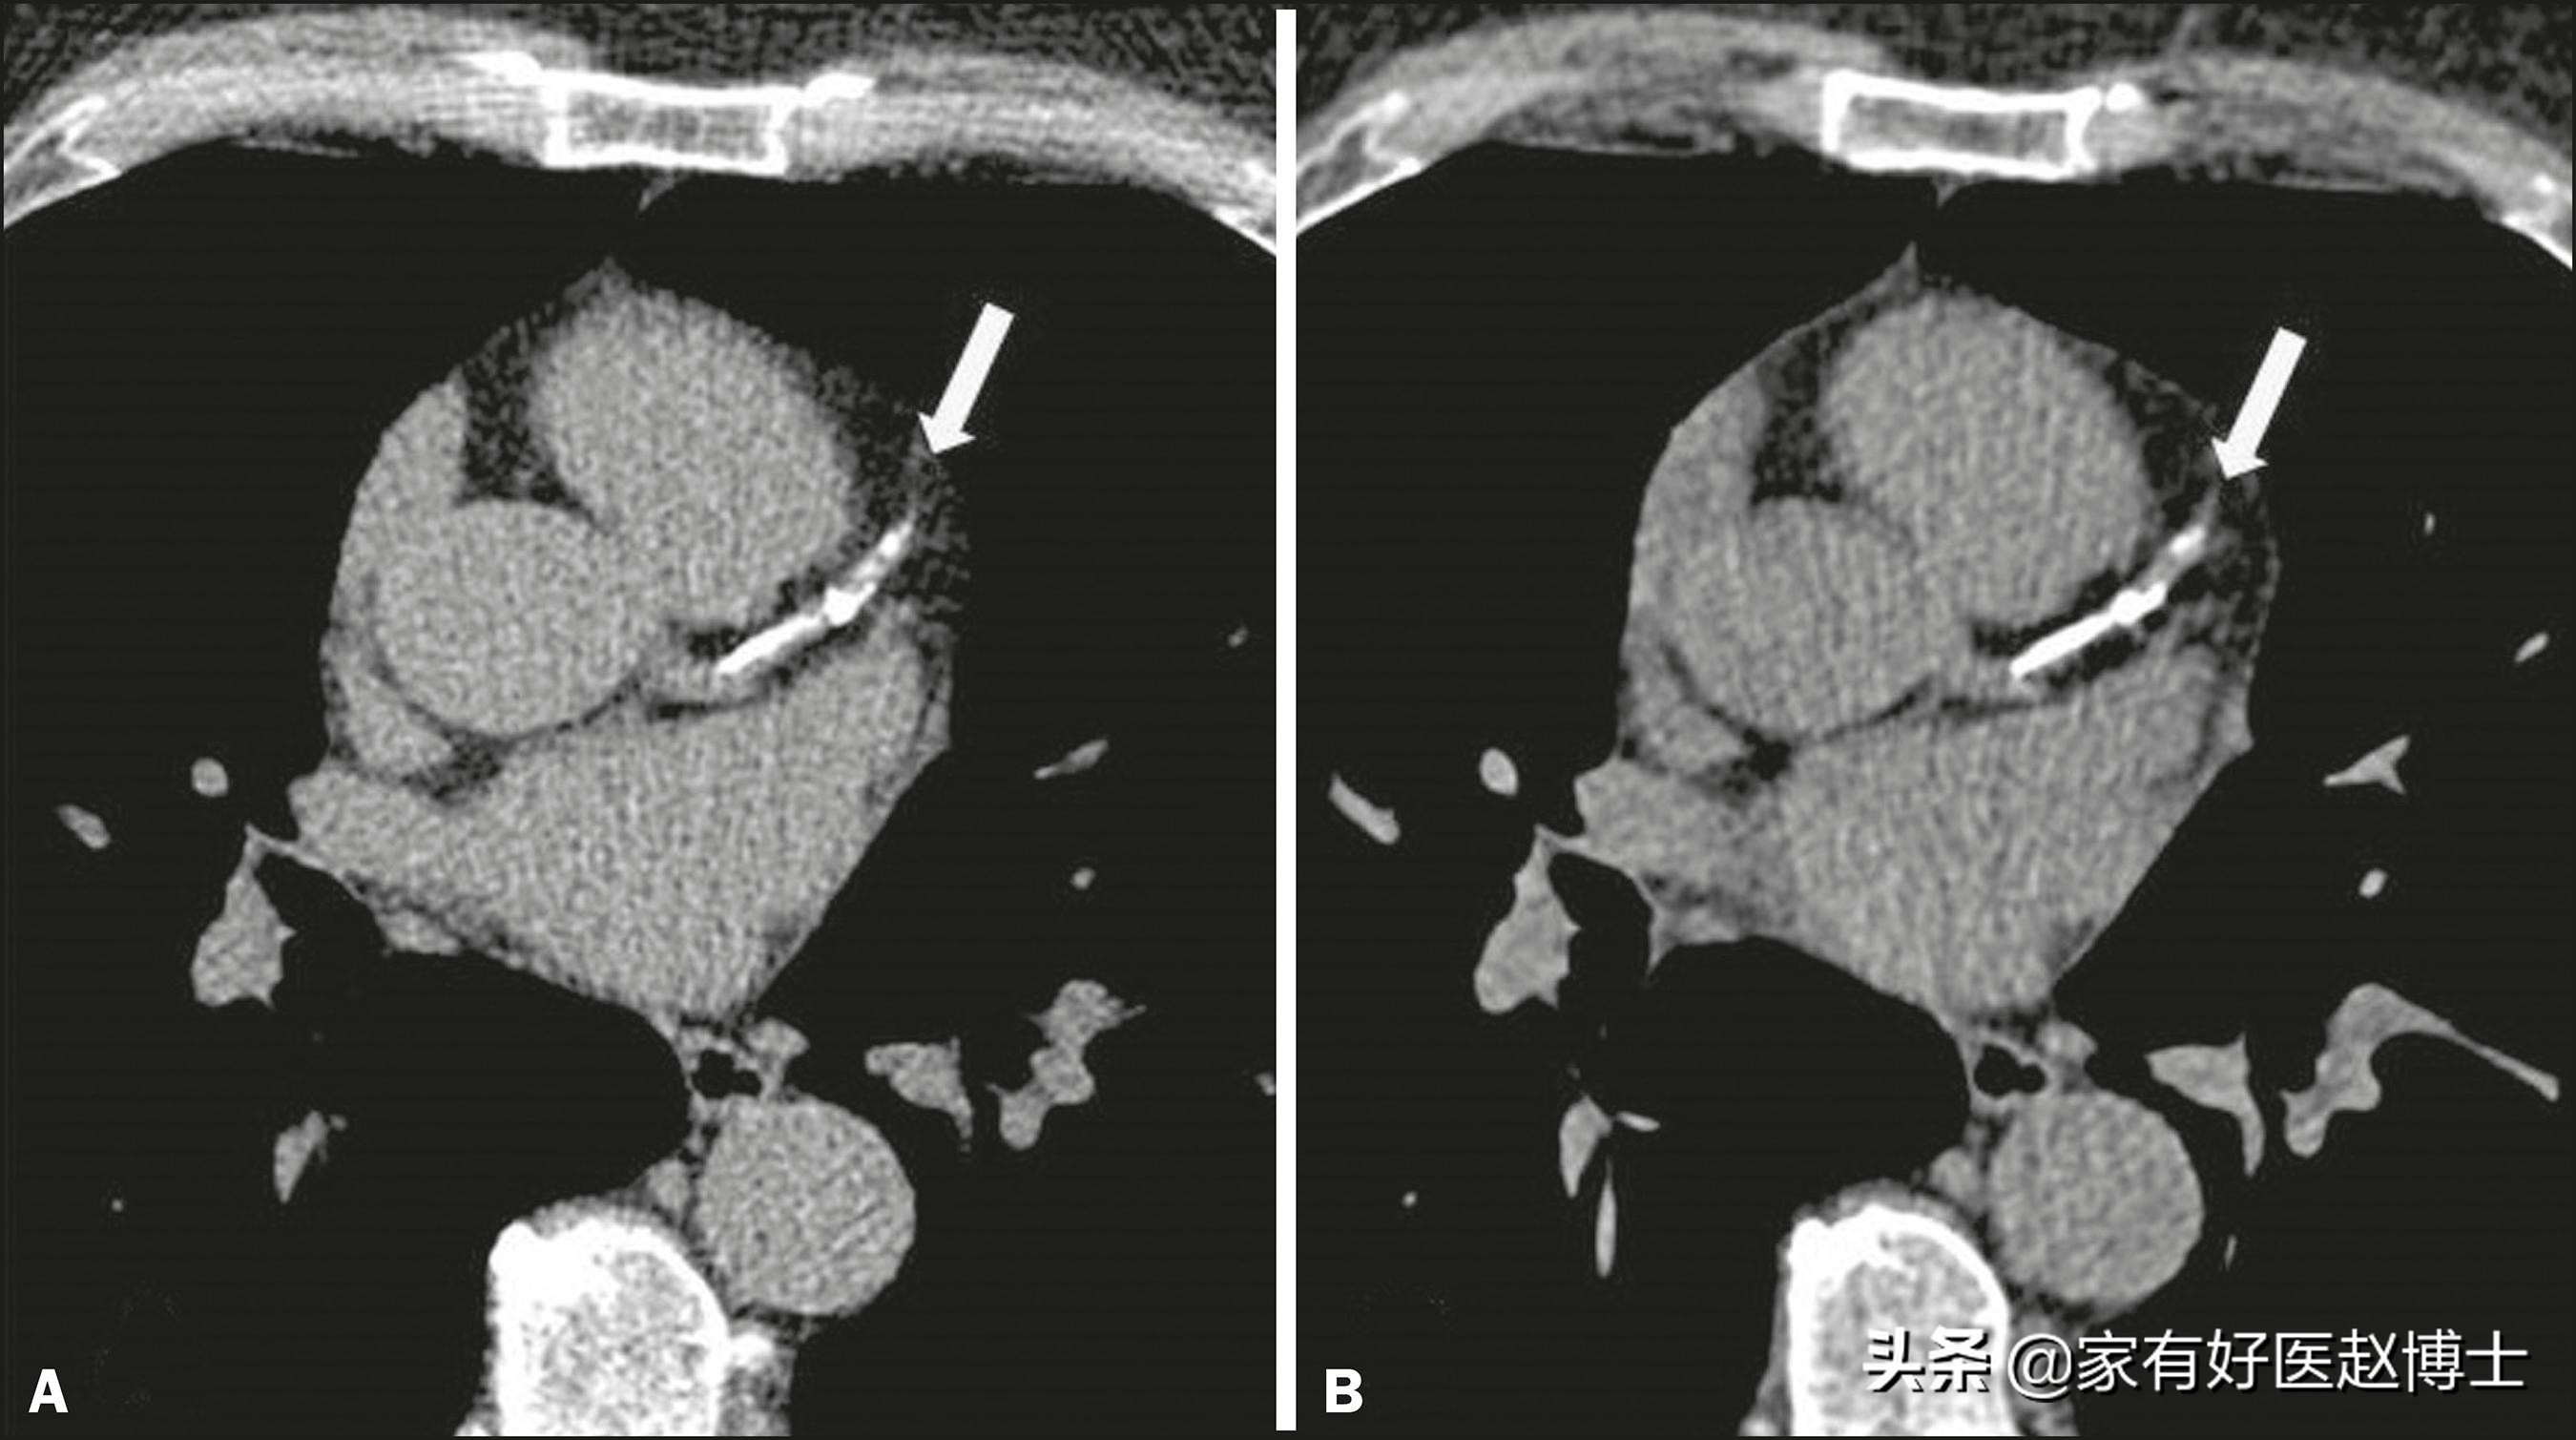

前面我们说到的,主要是一些重要器官当中出现的钙化,而还有一类钙化也在体检中常常遇到,这就是血管的钙化。偶尔候,肺部CT扫描可以看到主动脉或冠状动脉上的钙化,而颈动脉超声检查则可以识别出颈动脉内膜中的钙化。

动脉钙化与器官中的钙化不同,它并不会提示癌症风险,但是,它却常常意味着另一项足以致命的危险,这就是动脉硬化。大家需要记住很重要的一点,这就是:存在动脉钙化就等于存在动脉硬化。

因此,如果在体检中发现了动脉钙化,请仔细回顾一下:自己的血压、血糖、血脂等重要心血管指标是否都正常,如果存在异常,那应该尽早开始进行干预和治疗;哪怕这些指标都正常,那说明年龄和衰老这项单一因素已经造成了心血管系统的退化,要充分意识到自己正在面临不断增大的心血管风险。